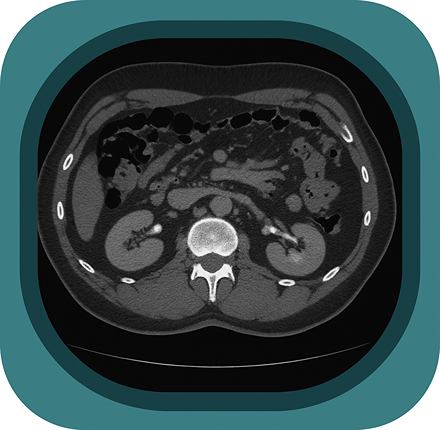

Explore full-body CT anatomy in 3 planes. Our high-resolution, carefully labelled images reveal micro-anatomy—ideal for radiologists, radiographers and surgeons.